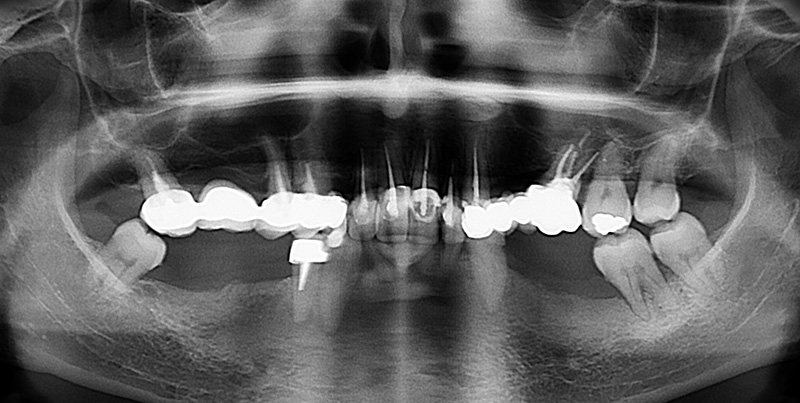

L’orthopantomographie souligne des traitements canalaires satisfaisants au niveau des dents 17, 15, 12, 11, 21, 23 et 26 mais insuffisants au niveau des dents 14, 22 et 44. En outre, il met en évidence la présence de foyers infectieux au niveau des dents 22 et 44 ainsi qu’une ostéolyse au niveau de la 37 (> 50 %). Les dents composant le bloc incisif mandibulaire présentent des racines très courtes non ancrées dans l’os alvéolaire.

Fig. 04 : orthopantomographie initiale.